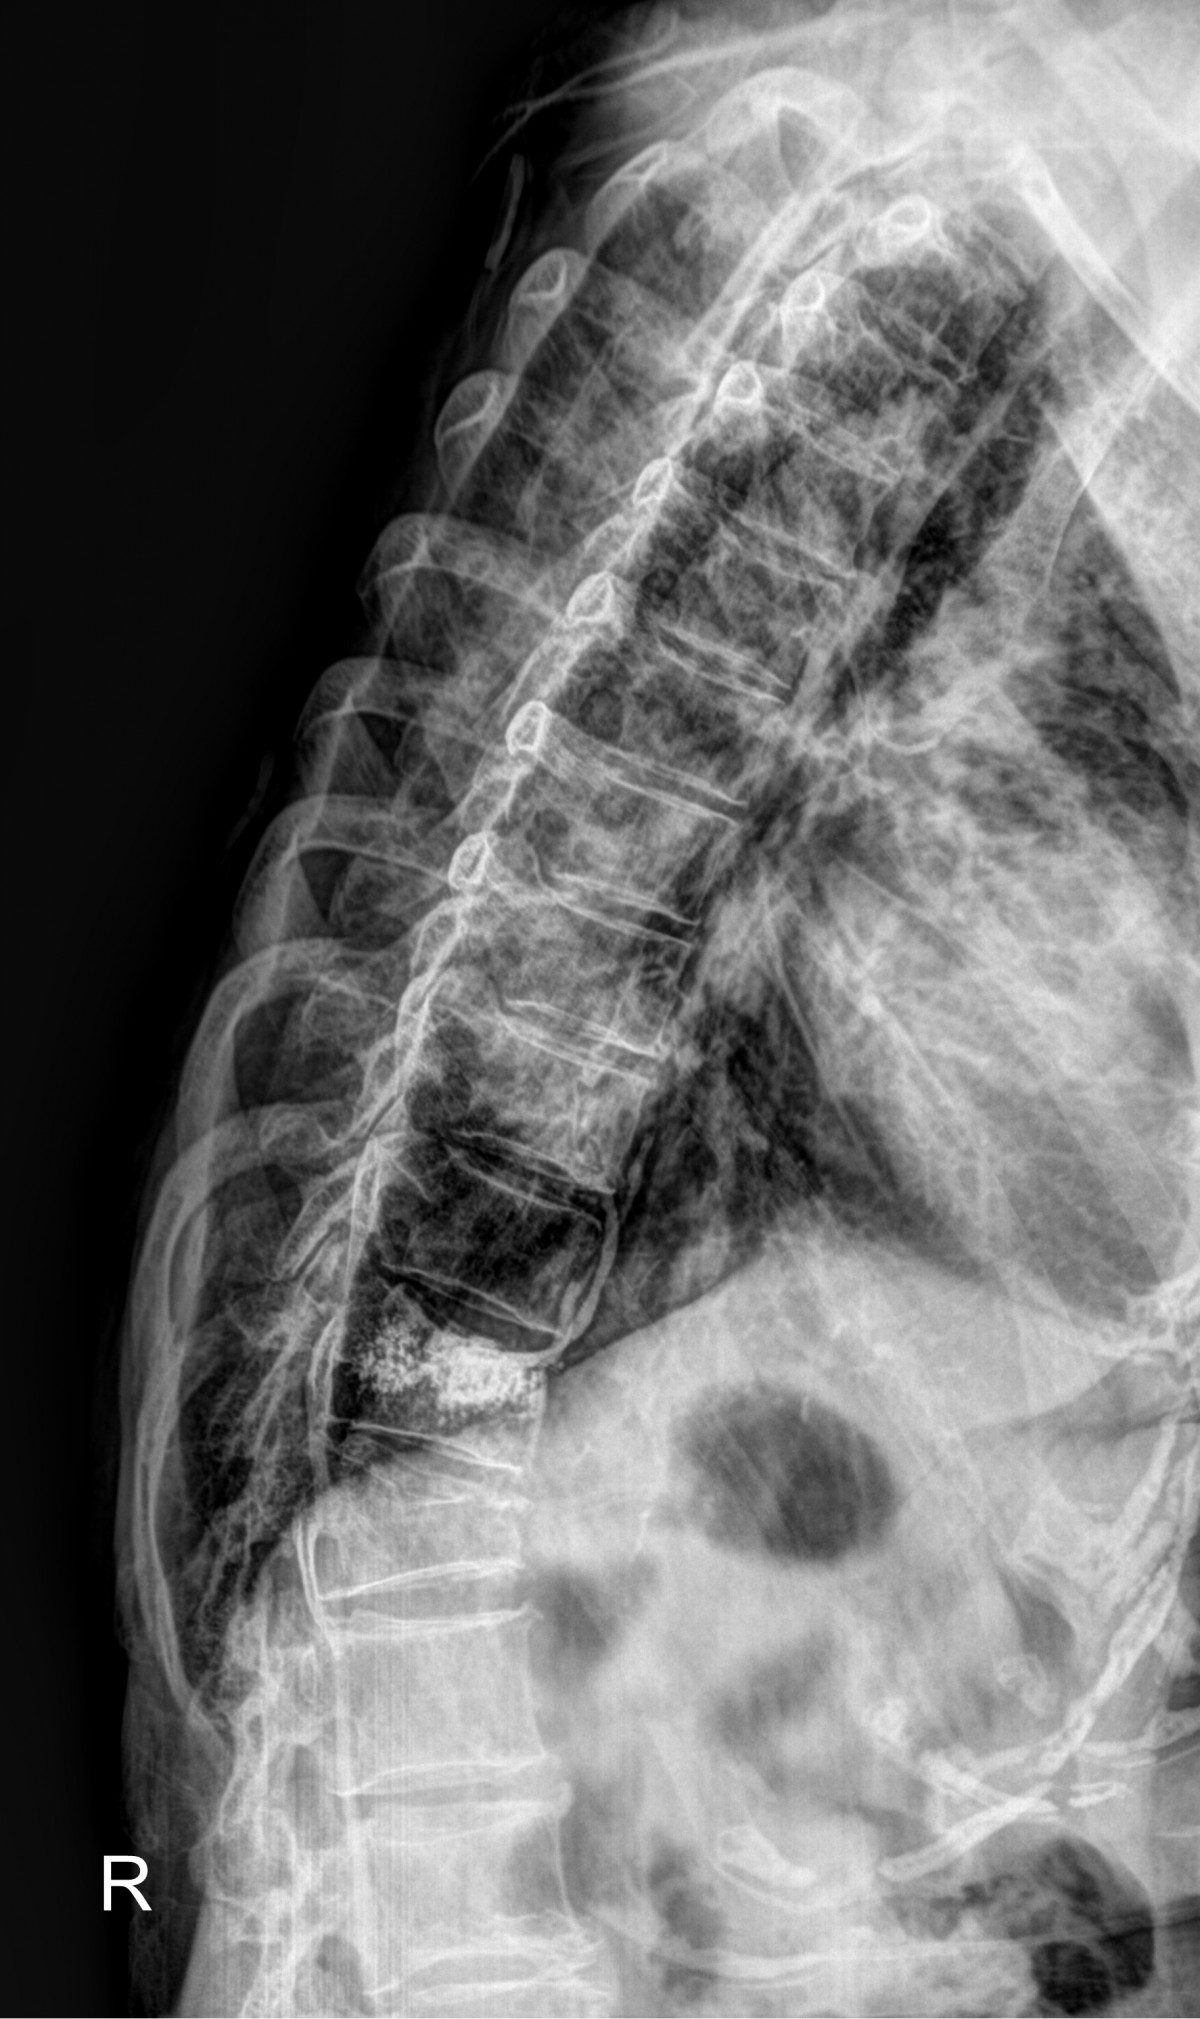

정지영원장님 흉추 골절 골시멘트 성형술 김월O 환자

작성자 최고관리자 댓글 0건 조회 688회 작성일 25-09-16 16:31

dae765e4d9ac96aee867c9d6292d8784_1758007905_4838.jpg